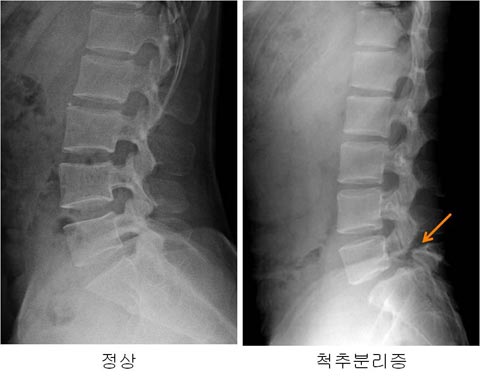

척추 분리증은 C자형으로 휘어진 요추에서 위 척추뼈와 아래 척추뼈가 떨어지지 않게 해주는 뼈(척추 후궁)에 금이 간 것을 말한다.

사진=안양튼튼병원 제공